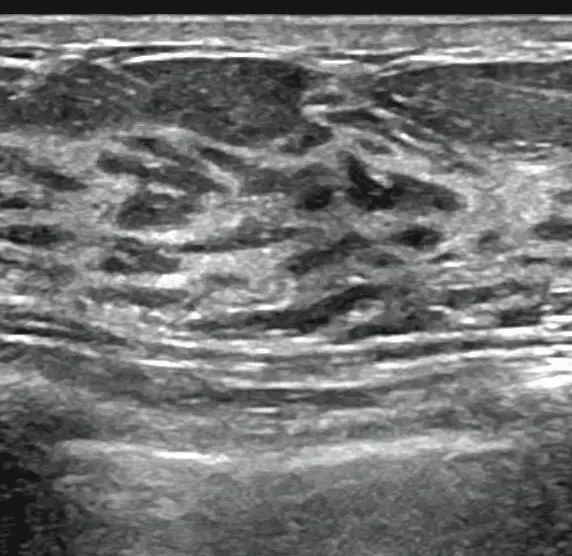

该分级主要从形态、方位、边缘、内部回声、后方特征、与周围组织关系、钙化等几方面描述乳腺肿物。

形态不规则、纵横比大于1、边缘模糊(成角、微小分叶、“蟹足状突起”)、不均质低回声、后方回声改变、结构紊乱侵犯周边组织、钙化均考虑为恶性标志。